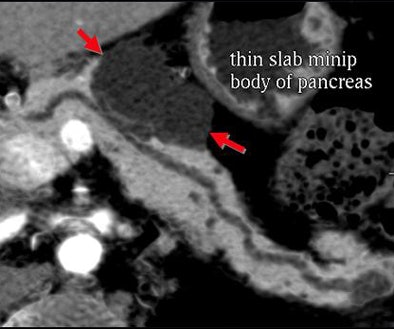

Certainly imaging-based diagnosis of the cysts has its limitations. For one thing, MDCT can diagnose six different pancreatic lesion types, including side branch intraductal papillary mucinous neoplasms (IPMNs), serous microcystic adenomas, epithelial cysts, mucinous cystic neoplasms, lymphatic cysts, and cystic islet cell tumors. But it can't always tell them apart.

Small cystic lesions not worrisome for malignancy under 3 cm include side branch IPMNs, and serous microcystic adenomas, which are easily characterized by their honeycomb matrix that is also easily seen on ultrasound, Jeffrey said.